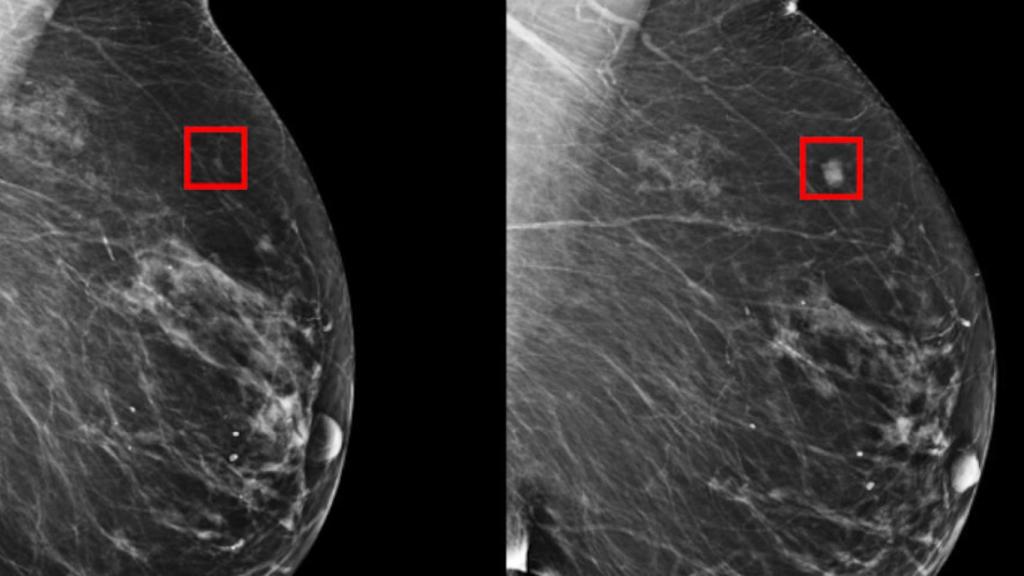

¿Qué es un mastógrafo?

Un mastógrafo es una herramienta que sirve para realizar una mastografía, un estudio de rayos “X” que se recomienda a mujeres de 40 a 69 años de edad, sin signos, ni síntomas de cáncer (asintomáticas) y tiene como propósito detectar anormalidades en las mamas, que no se pueden percibir por la observación o la palpación.